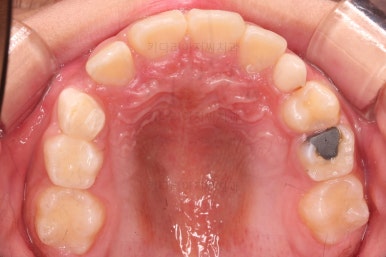

1. 초진

초진 시 입안의 모습입니다.

가장 눈에 띄는 건, 아랫니가 윗니보다 앞에 나와있는 부정교합인데요.